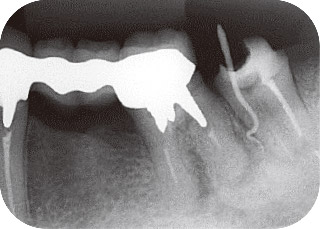

症例2:瘻孔の原因歯をデンタルから判定できなかった症例

46歳女性で、他院で下顎左側第二大臼歯の根管治療を開始したが、瘻孔が消えないために紹介で来院した。

瘻孔は患歯近心歯頸部に見られた(図4)。デンタルX線写真では患歯根尖に透過像が認められたが、瘻孔から挿入したガッタパーチャは近心根の途中で止まっていた(図5)。

また、下顎左側第一大臼歯遠心根の根尖部透過像とは独立しているように見えた。

図5 #37瘻孔からガッタパーチャポイントを挿入して撮影したデンタルX線写真